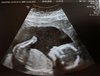

Malutka waży 260 g. Rączki, nóżki, wszystko na swoim miejscu :) Lekarka przyjrzała się dziecku tak dokładnie jakby to ona miała mi robić połówkowe, mówiła że tylko serduszka nie może sobie obejrzeć tak porządnie jak będzie je widać po 20 tygodniu.